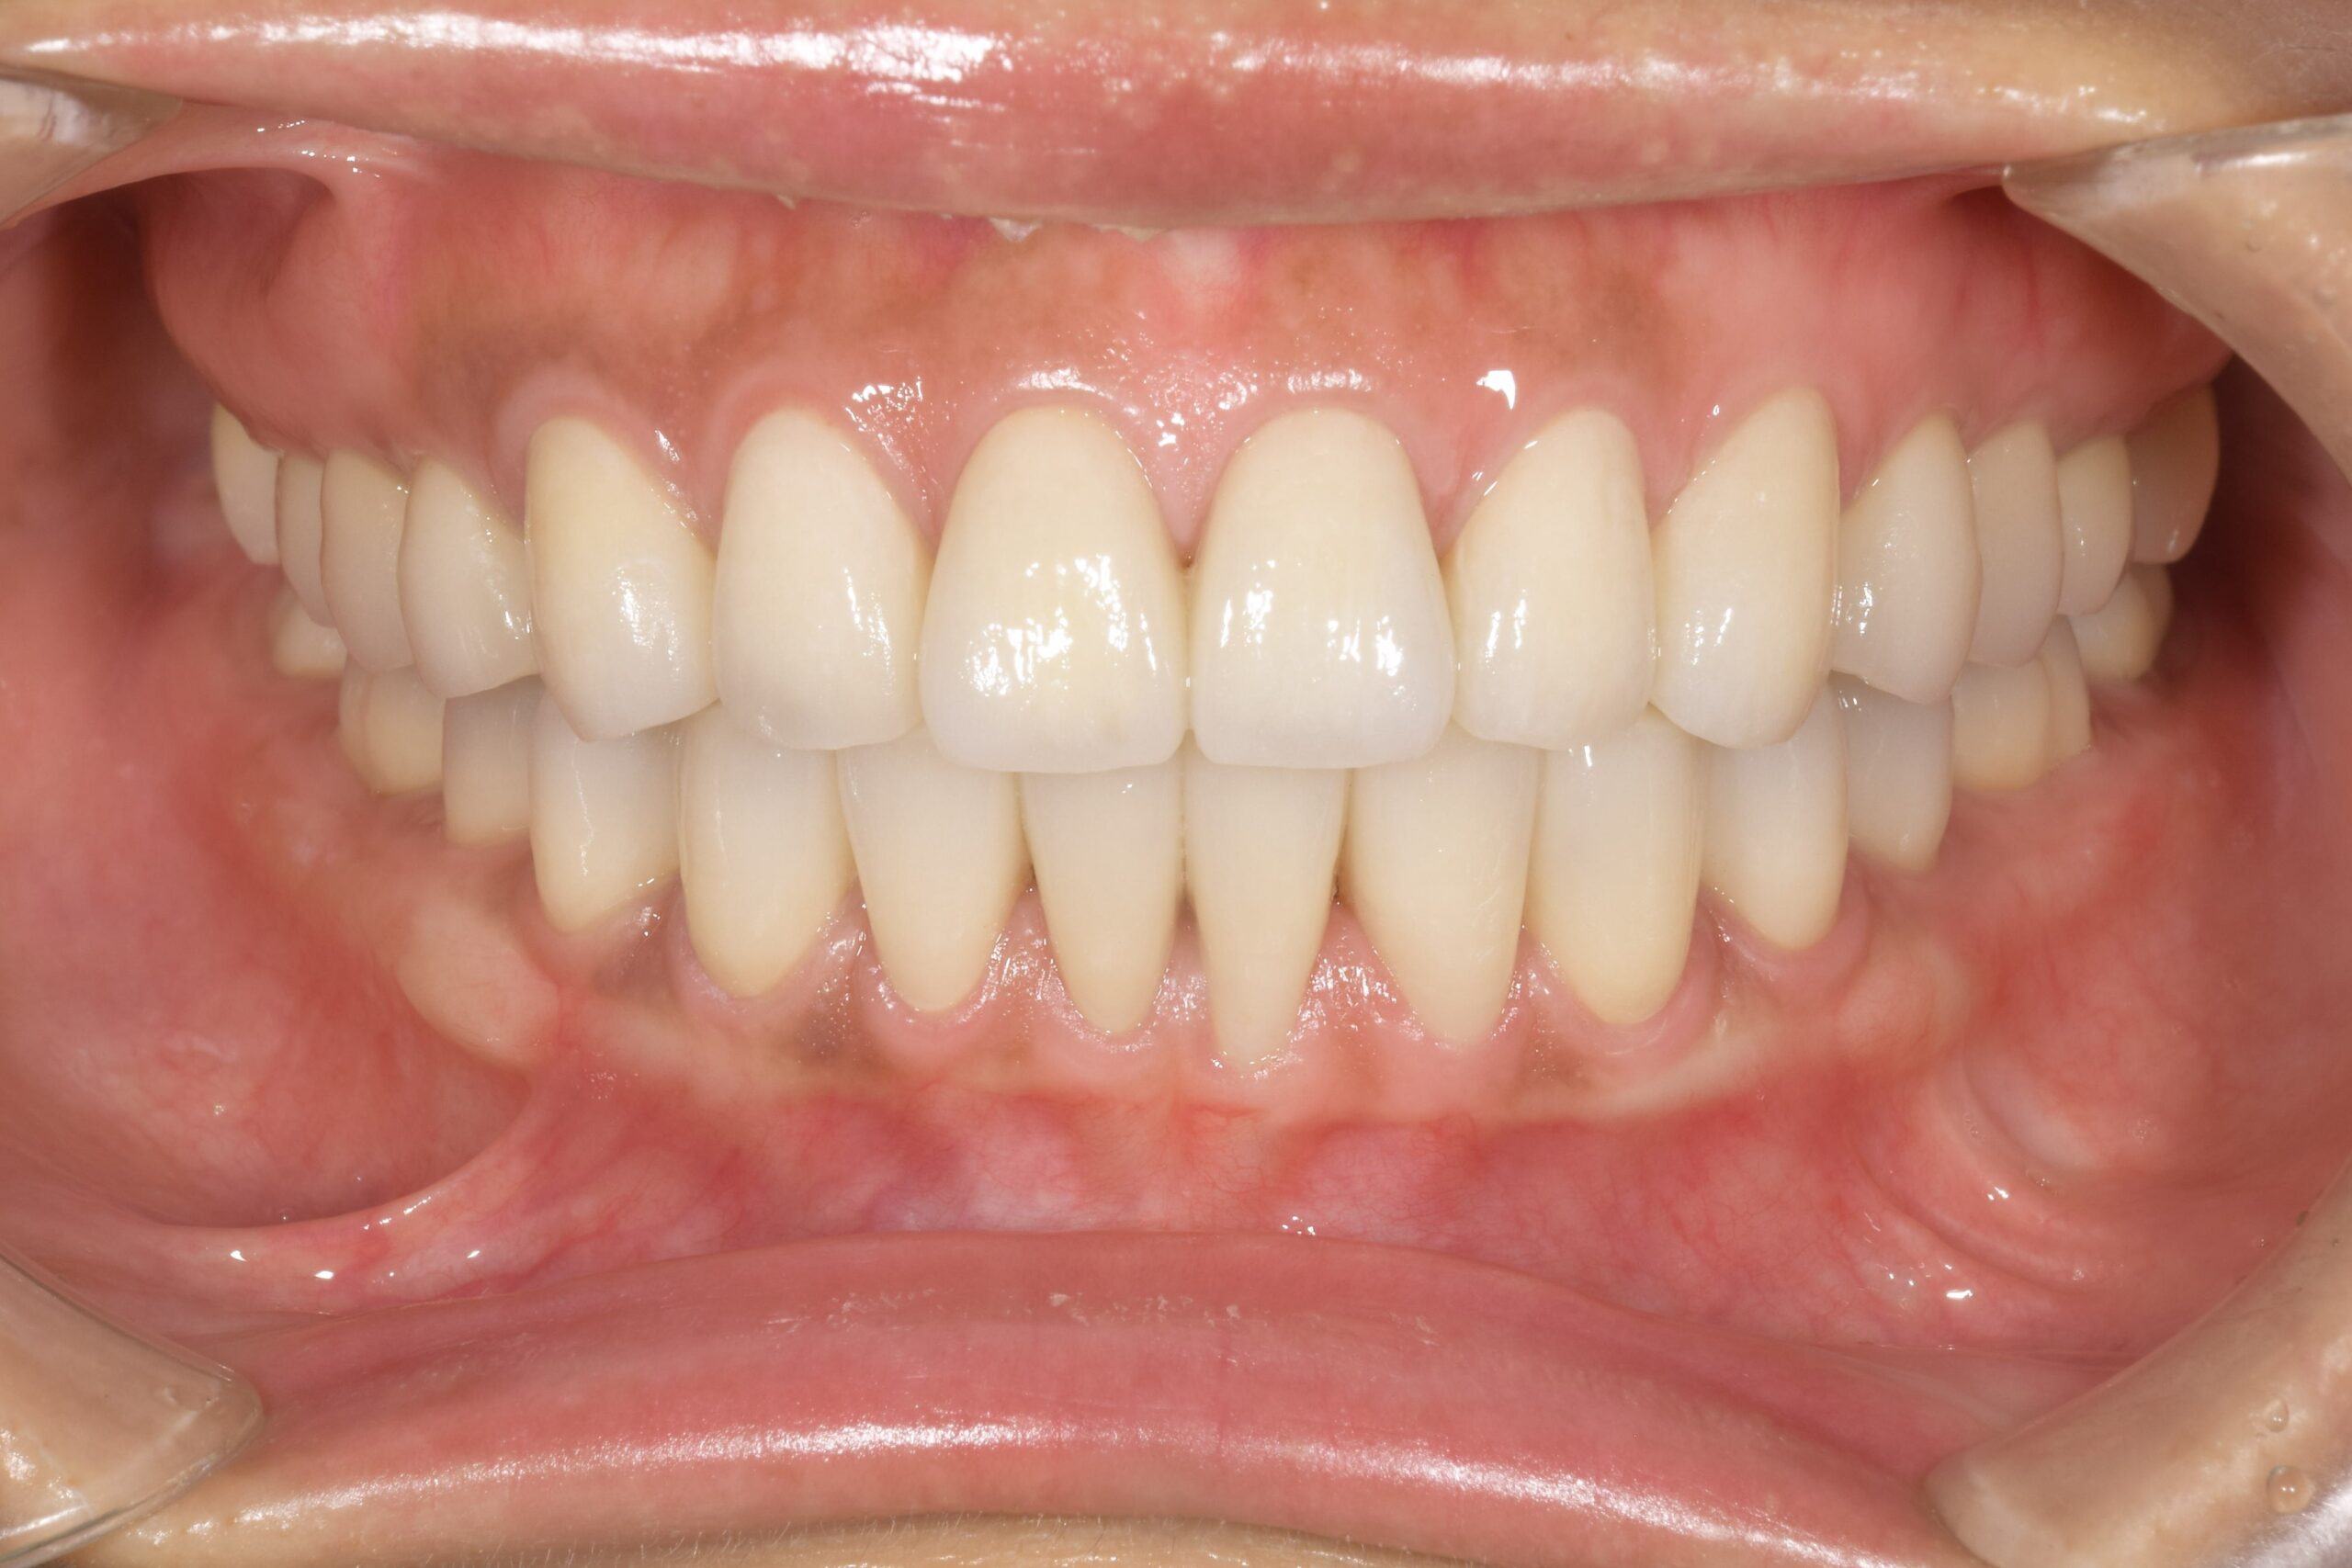

治療概要

| 症状 | 異常咬耗による咬合不全 審美障害 極度の知覚過敏 |

|---|---|

| 年齢 | 38歳 |

| 原因 | 極度の歯ぎしり 顎関節症(非復位性関節円板前方転位) |

| 治療法 | 歯周基本治療 全顎矯正治療にて適正顎位での咬合再構成 その後、全顎歯冠修復 |

| 治療費(目安) | 約500万円(料金改定前) |

治療前-治療後